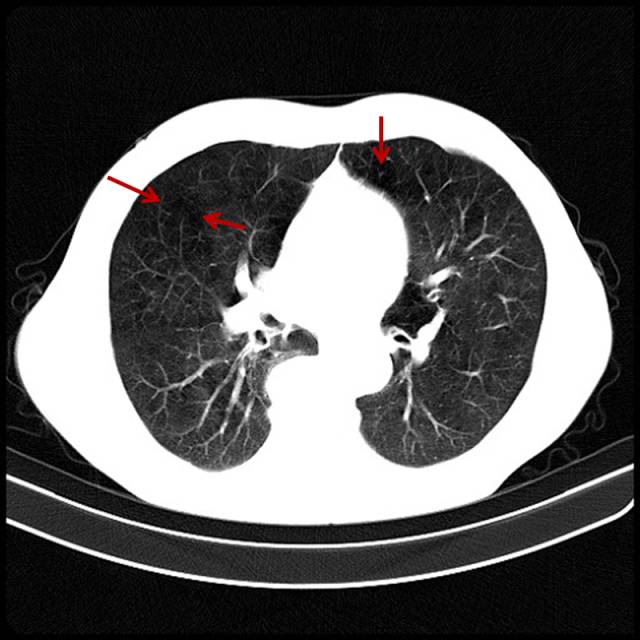

■ 吸烟导致的轻度肺气肿

男,32岁,16岁开始吸烟。